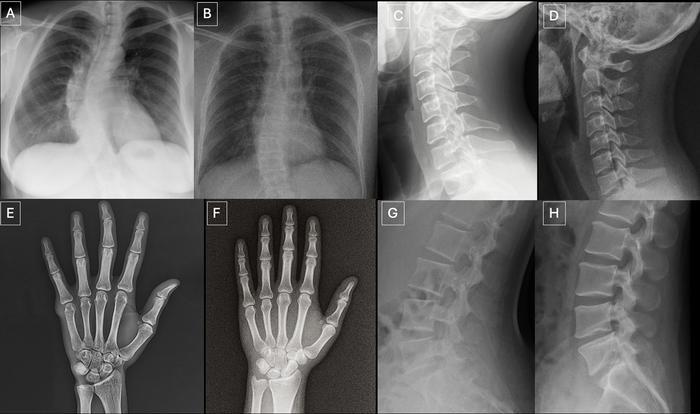

O estudo identificou padrões visuais recorrentes em imagens sintéticas: ossos excessivamente lisos, campos pulmonares simétricos demais e estruturas vasculares uniformes de forma não natural. Embora úteis como pistas, esses artefatos tendem a desaparecer à medida que os modelos generativos evoluem.